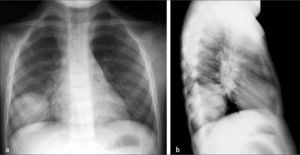

La radiografía (Rx) de tórax se considera como el mejor método diagnóstico en esta patología, de valor tanto desde un punto de vista clínico como epidemiológico (Figura 1) (1,4). Estudios reportan que en los pacientes en que se solicitó una Rx de tórax por sospecha de neumonía se produjeron cambios en el diagnóstico hasta en un 20% de los casos y en el manejo, hasta en un 30% de los casos (1). Cuando se dispone del recurso, la Rx debiera solicitarse en niños con: sospecha de neumonía cuando existe clínica dudosa o ambigua, síndrome febril sin foco, neumonía de curso prolongado, antecedente de neumonías anteriores, neumonía que no responde a tratamiento antibiótico o sospecha de complicaciones (3).

El control radiográfico no debiera ser la regla debiendo reservarse para los casos en que los síntomas son persistentes o recurrentes y pacientes con condiciones clínicas especiales que planteen la posibilidad de una evolución menos favorable, como inmunodeficiencias o fibrosis quística (9). La neumonía redonda constituye una condición en la que se acepta el control rutinario dado que plantea diagnóstico diferencial con patologías congénitas y adquiridas. La resolución de las imágenes de condensación en neumonías bacterianas es más rápida en el niño que en el adulto, habitualmente 7 a 10 días en cuadros no complicados (4) (Figura 2).